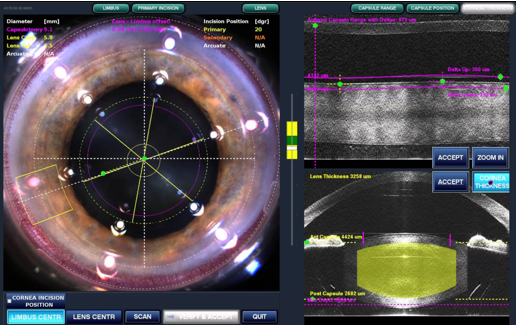

一旦有白內障且影響到日常生活,可依醫師專業建議接受白內障手術治療。目前主流的微切口超音波乳化術,是以超音波乳化探頭,經由角膜約2.2-2.4微米的傷口,將白內障震碎後吸出,再根據患者需求植入不同功能的人工水晶體便完成。手術過程約15-20分鐘,在局部麻醉下即可進行且不須住院。但少部分患者因畏懼手術或仍存有過往「白內障要完全成熟才開刀」的錯誤觀念,以致增加手術的困難度跟術後恢復時間。目前多家醫院與診所更引進最新「飛秒雷射白內障前置手術系統」,利用電腦即時監控,可更加提高手術準確度與安全性。

圖二:新式飛秒雷射白內障前置手術系統提供患者更準確安全的效果